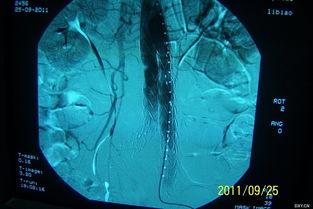

主动脉支架,听起来是不是很专业?没错,它是一种用于治疗主动脉夹层的医疗器械。主动脉夹层是一种严重的血管疾病,如果不及时治疗,后果不堪设想。而国产主动脉支架,就是用来修复受损的主动脉,防止病情恶化的“救星”。

这个国产主动脉支架的视频,让我对它有了更深入的了解。首先,它采用了先进的3D打印技术,可以根据患者的具体情况进行个性化定制。这样一来,支架的贴合度更高,治疗效果自然也就更好。

视频中的案例让我印象深刻。有一位名叫李先生的病人,因为主动脉夹层导致生命垂危。在医生的建议下,他选择了国产主动脉支架进行治疗。经过一段时间的恢复,李先生的病情得到了明显改善,生活也恢复了正常。

这个案例充分说明了国产主动脉支架在临床治疗中的重要作用。事实上,国产主动脉支架已经广泛应用于国内外多家医院,为无数患者带来了希望。